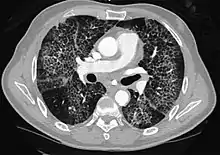

CT showing diffuse ground-glass opacities in periphery of both lungs in patient with COVID-19.